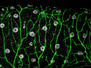

Imagine travelling through the brain, being able to map differences between individuals and perhaps even easily pinpointing the areas where the brain’s connections have ‘gone wrong’ in diseases such as Alzheimer’s and schizophrenia. By combining rapid automated electron microscopy analysis of normal and diseased brain tissue with new imaging technology neuroscientists are working towards doing exactly that. Pictured is a composite of false-coloured electron microscopy image of vanishingly thin sections of mouse brain tissue. Within the cylindrical area – which is ten times smaller than a typical sand grain – more than 500 nerve fibres and their junctions or synapses can be seen in unprecedented detail. With technology like this our most fascinating organ is surrendering more secrets of its structure and activity.